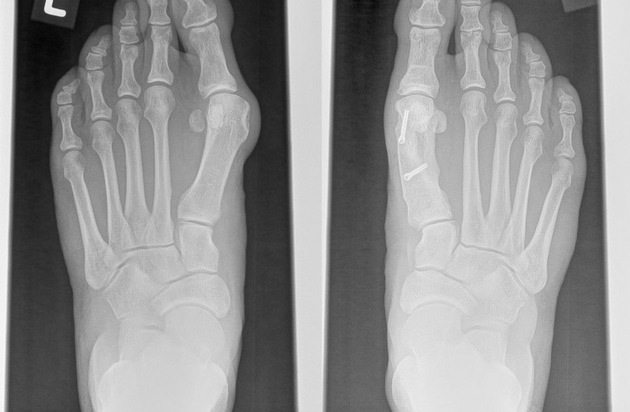

MAGNEZIX® - das Metallimplantat, das zu Knochen wird: Folgeoperationen zur Metallentfernung bei Hallux valgus nicht mehr nötig / Hallux Valgus (links), Behandlung mit MAGNEZIX®-Schrauben (rechts, bioabsorbierbare metallische Implantate), Fußchirurgie, Hammerzeh, Ballenzeh. Weiterer Text über ots und www.presseportal.de/nr/122353 / Die Verwendung dieses Bildes ist für redaktionelle Zwecke honorarfrei. Veröffentlichung bitte unter Quellenangabe: "obs/Syntellix AG"